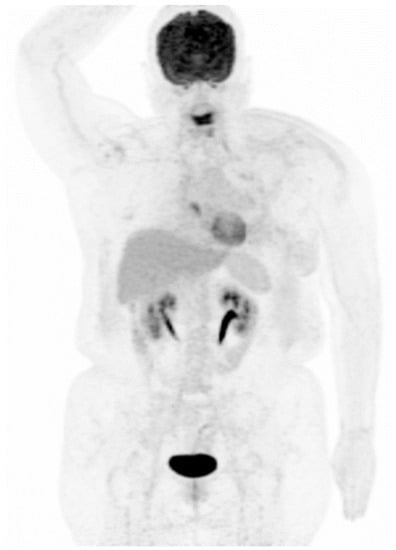

Figure 3. Maximum-intensity-projection image of FDG PET/CT. Follow-up FDG PET/CT scan 8 months later revealed an almost complete response of prior left breast cancer with multiple nodal, pulmonary, and bony metastases, with stationary status as compared with the second scan.

The patient was treated with palliative chemotherapy with paclitaxel plus cisplatin for breast cancer. In addition, palliative radiotherapy for local pain control (left breast, left scapula, sternum, and spine) was given. A second follow-up FDG PET/CT scan 3 months later during treatment revealed marked regression of prior breast cancer and multiple nodal, pulmonary, and bony metastases. A series of follow-up FDG PET/CT scans 8 months (Figure 3) and 11 months later revealed the stationary status of the post-treated breast cancer and metastatic lesions. However, the patient presented with progressive slurred speech, right arm weakness, and right leg weakness 17 months after the first FDG PET/CT scan. Contrast-enhanced magnetic resonance imaging of the brain demonstrated at least five tumors with nodular or rim-like enhancement and perifocal vasogenic edema in the right parietal lobe, right occipital lobe, left precentral gyrus, and right cerebellum, suggesting brain metastasis. Rapid progression of the disease was noted later on. Thus, the patient and her family decided to receive hospice care.

The prognosis of synchronous malignancies is evaluated separately according to the stage of each malignancy. Our patient was diagnosed with imaging stage T4bN2M1 (stage IV) breast cancer and pathological stage T1 sigmoid colon cancer. Early detection and recognition of the second primary malignancy are crucial and may bring benefits to the patient. After the removal of the malignant colonic polyp via endoscopic mucosal resection, our patient received palliative chemotherapy with paclitaxel plus cisplatin for breast cancer. A follow-up FDG PET/CT scan 3 months later during treatment revealed marked regression of prior breast cancer and multiple nodal, pulmonary, and bony metastases. A series of follow-up FDG PET/CT scans 8 months and 11 months later revealed the stationary status of the post-treated breast cancer and metastatic lesions. Brain metastasis with rapid disease progression was noted 17 months after the first FDG PET/CT scan, consistent with the poor prognosis of triple-negative breast cancer. Nevertheless, no evidence of colon cancer recurrence was noted on FDG PET/CT scan throughout the patient’s breast cancer disease course.